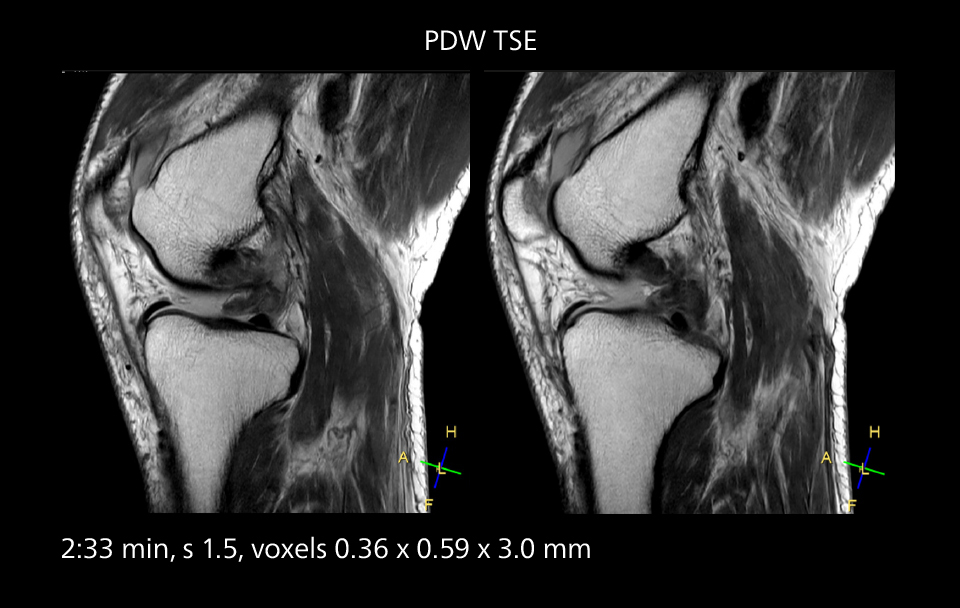

MRI of the knee

Images showing a posterior cruciate ligament (PCL) tear, a detached medial collateral ligament (MCL) on the tibial side and an intact anterior cruciate ligament (ACL). SmartPath to Elition X helped reduce scan time compared to previous imaging while maintaining resolution.

An example of increased imaging speed is in knee studies. “There is a definite scan time reduction for T2* mFFE and proton density TSE – both of these sequences benefit from much shorter repetition times,” he reports.

Overall, imaging time per sequence has been reduced since the Elition X upgrade. This can help reduce the risk of patient movement and the need for rescans.